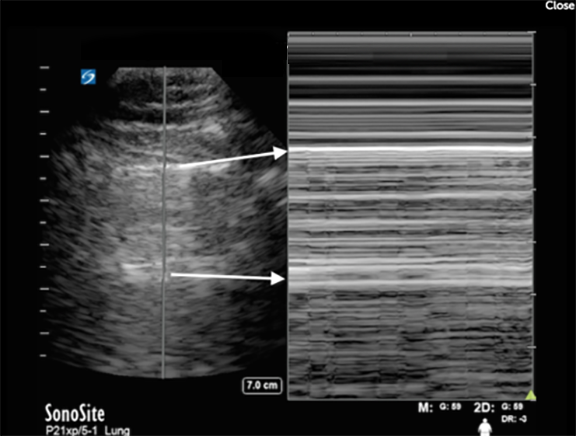

RUSH Lung Phased M-Mode Sea Shore Sign Image